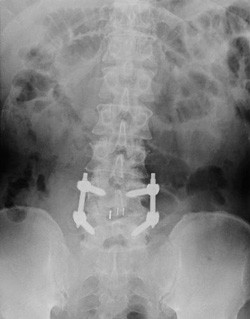

腰痛の手術をしたのに、腰痛が良くならないという相談をよく受けます。原因はいろいろあるのですが、動作で悪化する腰痛は腰痛ベルトで治すことができます。お医者さまが見ているMRIは静止画像ですから、動作の異常を発見できないことが結構あります。早い時期に腰痛ベルトを使ってケアしましょう。